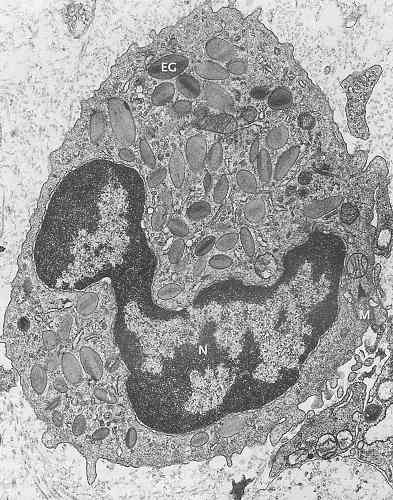

TEM opname van een erytrocyt. Links origineel, rechts ingekleurd met Fotoshop.

Opname van Carsten Dittmayer, Universiteit van Berlijn.

Klik op de afbeelding voor een vergroting.